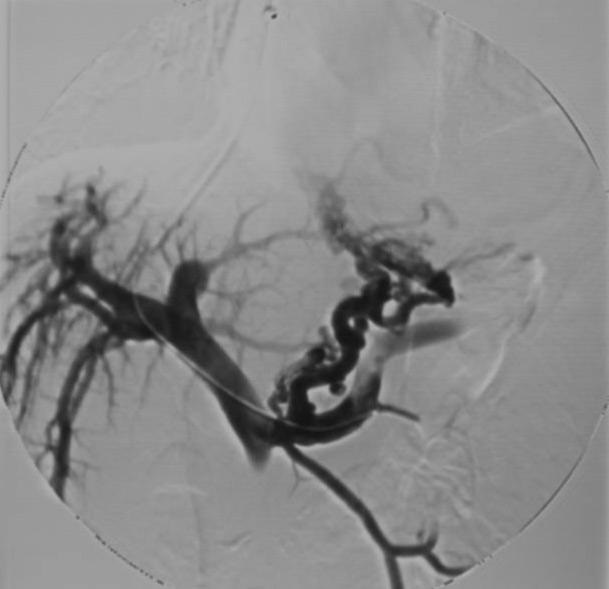

(9)胃冠状静脉栓塞术

TIPS 并发症 (1)分流通道狭窄:多为后期并发症,主要原因胆汁污染(Biliary contamination)和新生内膜异常增生。

通常可以ePTEF覆膜支撑架减少再狭窄;裸支撑架1年初始开通率16~50%;到两年时开通率下降至5%;作为密切随访和反复再干预(球囊扩张或新支撑架植入)情况下,开通率可以保持2年90%【4~6】。 克服裸支撑架再狭窄缺陷,考虑使用覆膜支撑架